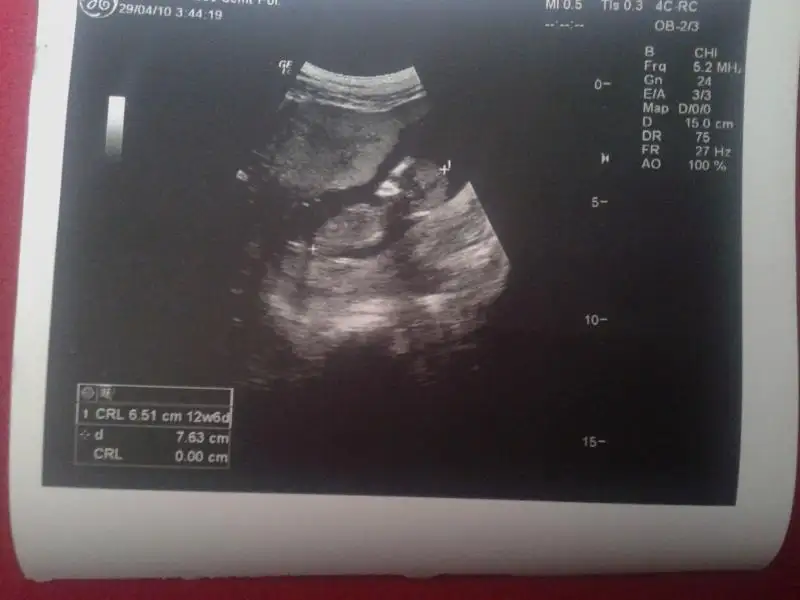

benimde bebişim 12 haftalık..lütfen cinsiyetine yorum alabilirmiyimEki Görüntüle 923096 [/QUO

ya başlık emir kipi gibi olmuş.kusura bakmayın :) merak ediyorum,lüften cevap alabilimiyim..